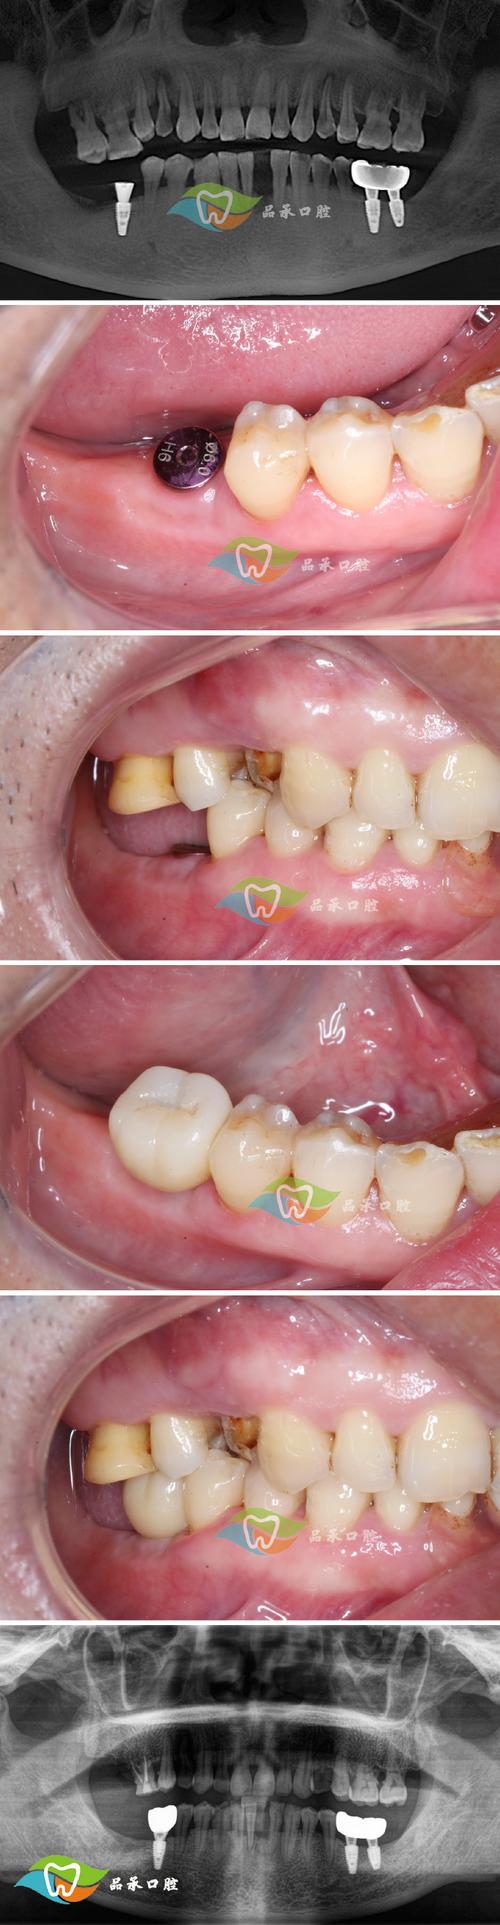

- 种植体周围骨吸收: 失败的种植体周围会发生骨溶解和吸收,导致原本为种植准备的骨量减少。

- 骨缺损: 取出失败的种植体后,常会留下骨缺损,骨量不足使得后续重新种植变得困难,甚至需要复杂的骨增量手术(如植骨、骨引导再生等)。

- 牙龈退缩: 骨吸收常伴随牙龈退缩,导致种植体颈部暴露,影响美观和清洁。